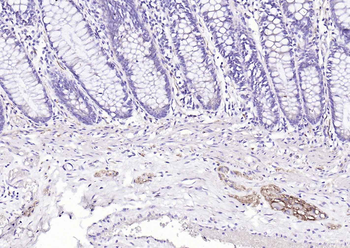

CD56 Antibody

Catalog Number: orb1317086

| Catalog Number | orb1317086 |

|---|---|

| Category | Antibodies |

| Description | Mouse monoclonal antibody to CD56 (NCAM1) |

| Species/Host | Mouse |

| Clonality | Monoclonal |

| Clone Number | OTI1C7 |

| Tested applications | IHC, WB |

| Reactivity | Human, Mouse, Rat |

| Isotype | IgG2a |

| Immunogen | Human recombinant protein fragment corresponding to amino acids 20-718 of human NCAM1 (NP_851996) produced in HEK293T cell. |

| Antibody Type | Primary Antibody |

| Dilution range | WB 1:2000, IHC 1:150 |

| Conjugation | Unconjugated |

| MW | 94.4 kDa |

| Target | CD56 |

| UniProt ID | P13591 |

| NCBI | NM_181351 |

| Storage | Maintain refrigerated at 2-8°C for up to 2 weeks. For long term storage store at -20°C in small aliquots to prevent freeze-thaw cycles. |

| Note | For research use only |

| Expiration Date | 12 months from date of receipt. |